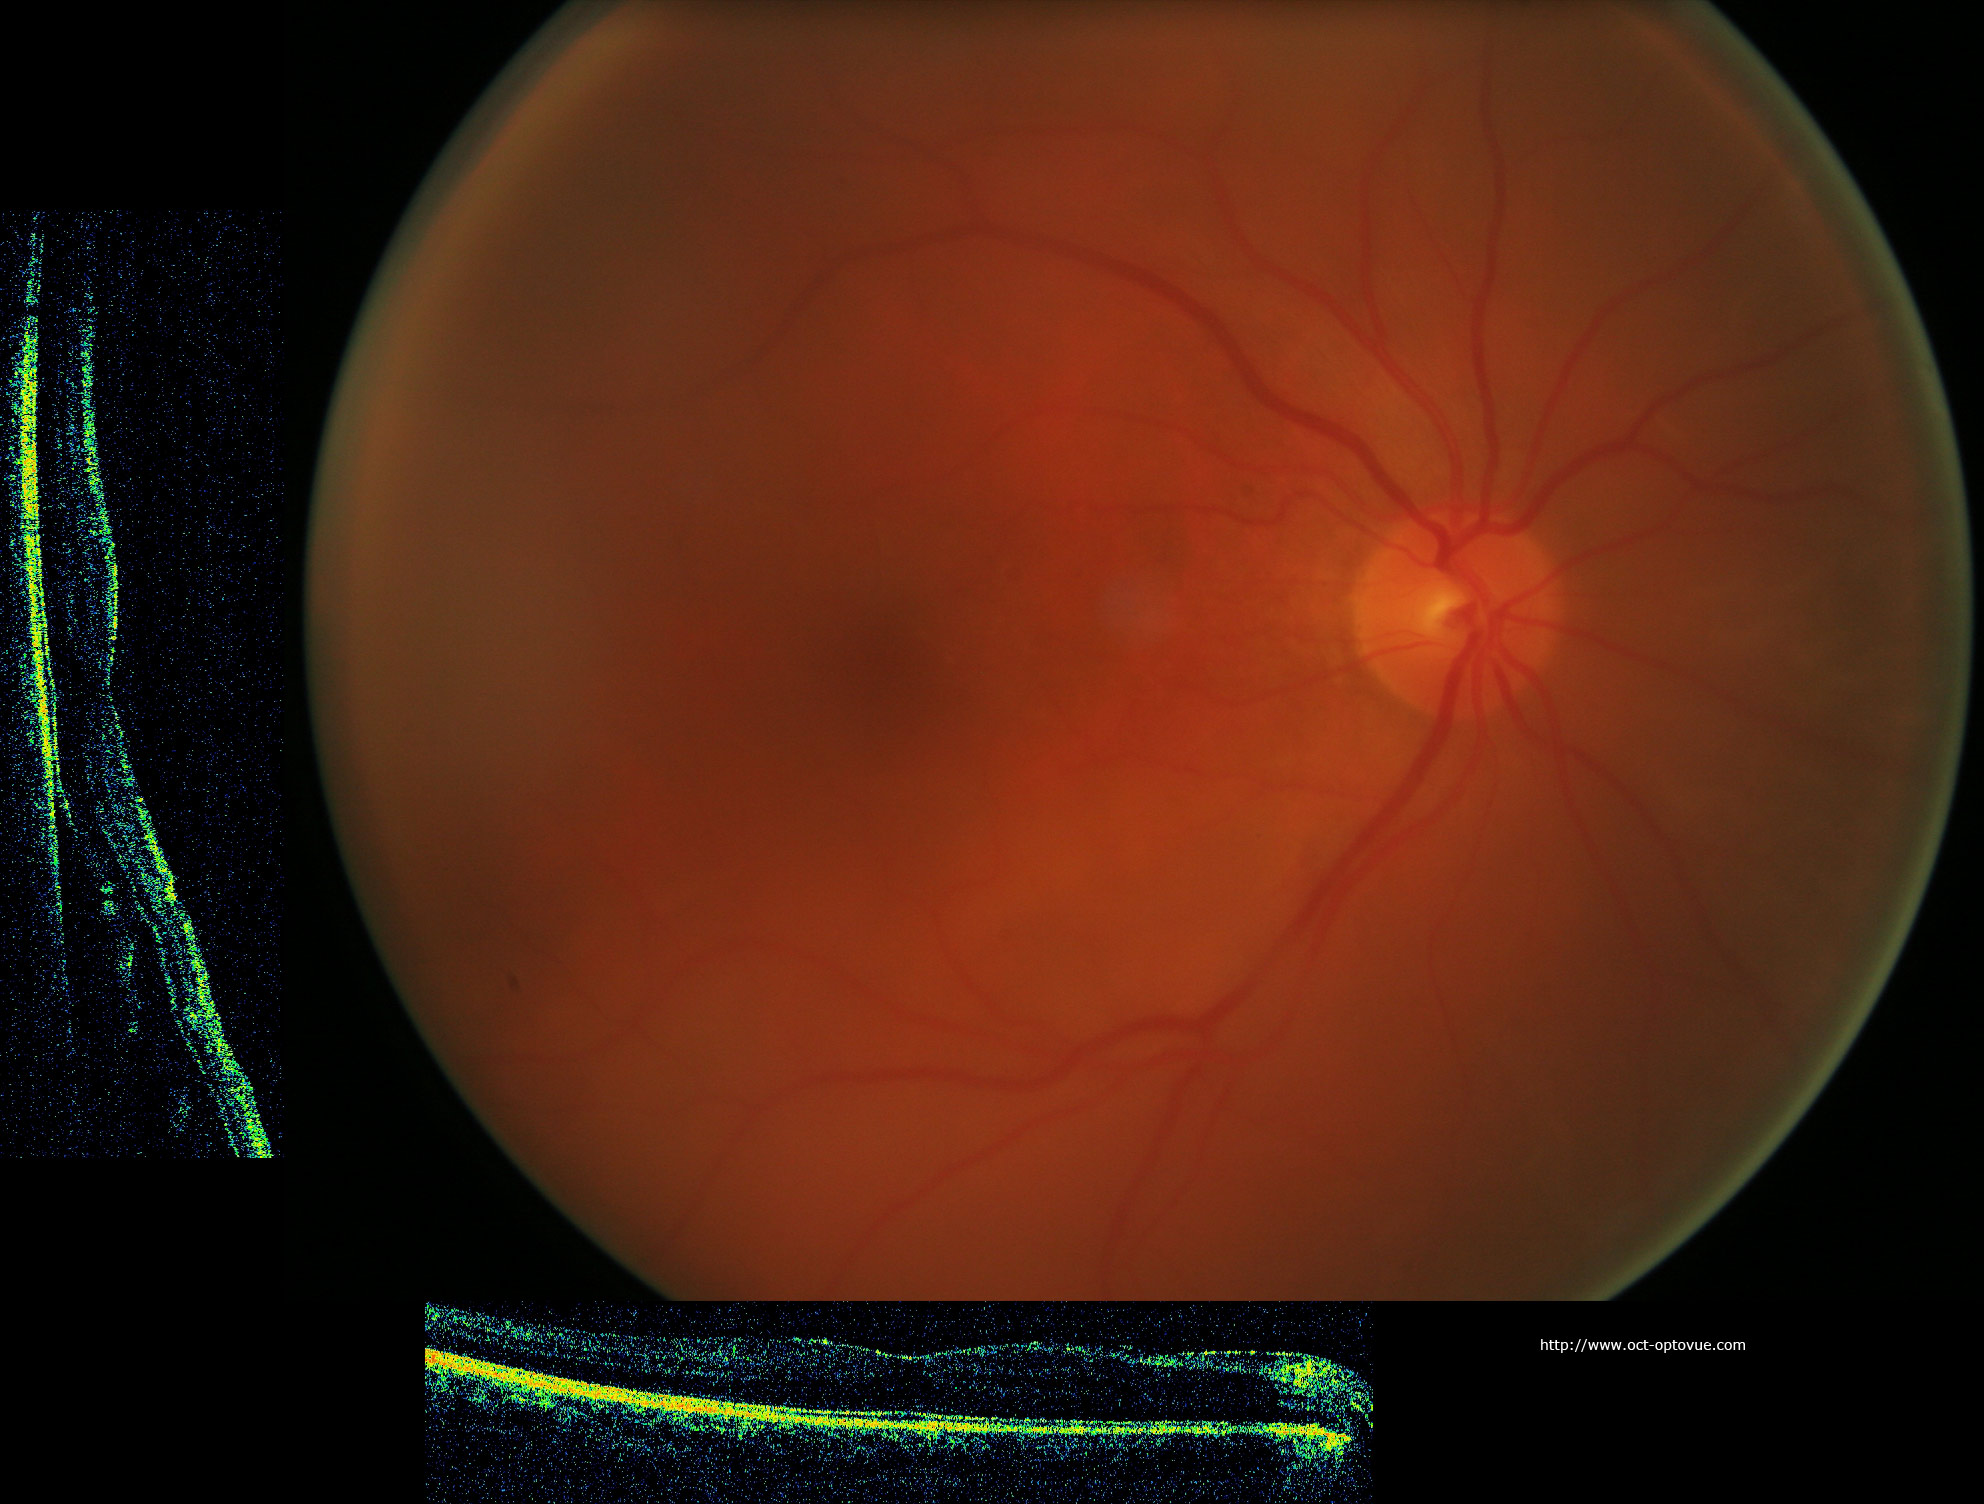

www.docteur-leroy.comDécollement Rétine

www.docteur-leroy.comDécollement Rétine

www.retinesud.frDécollement Rétine

www.retinesud.frDécollement Rétine

www.oct-optovue.comLe Décollement De Rétine • Vision Dix

www.oct-optovue.comLe Décollement De Rétine • Vision Dix